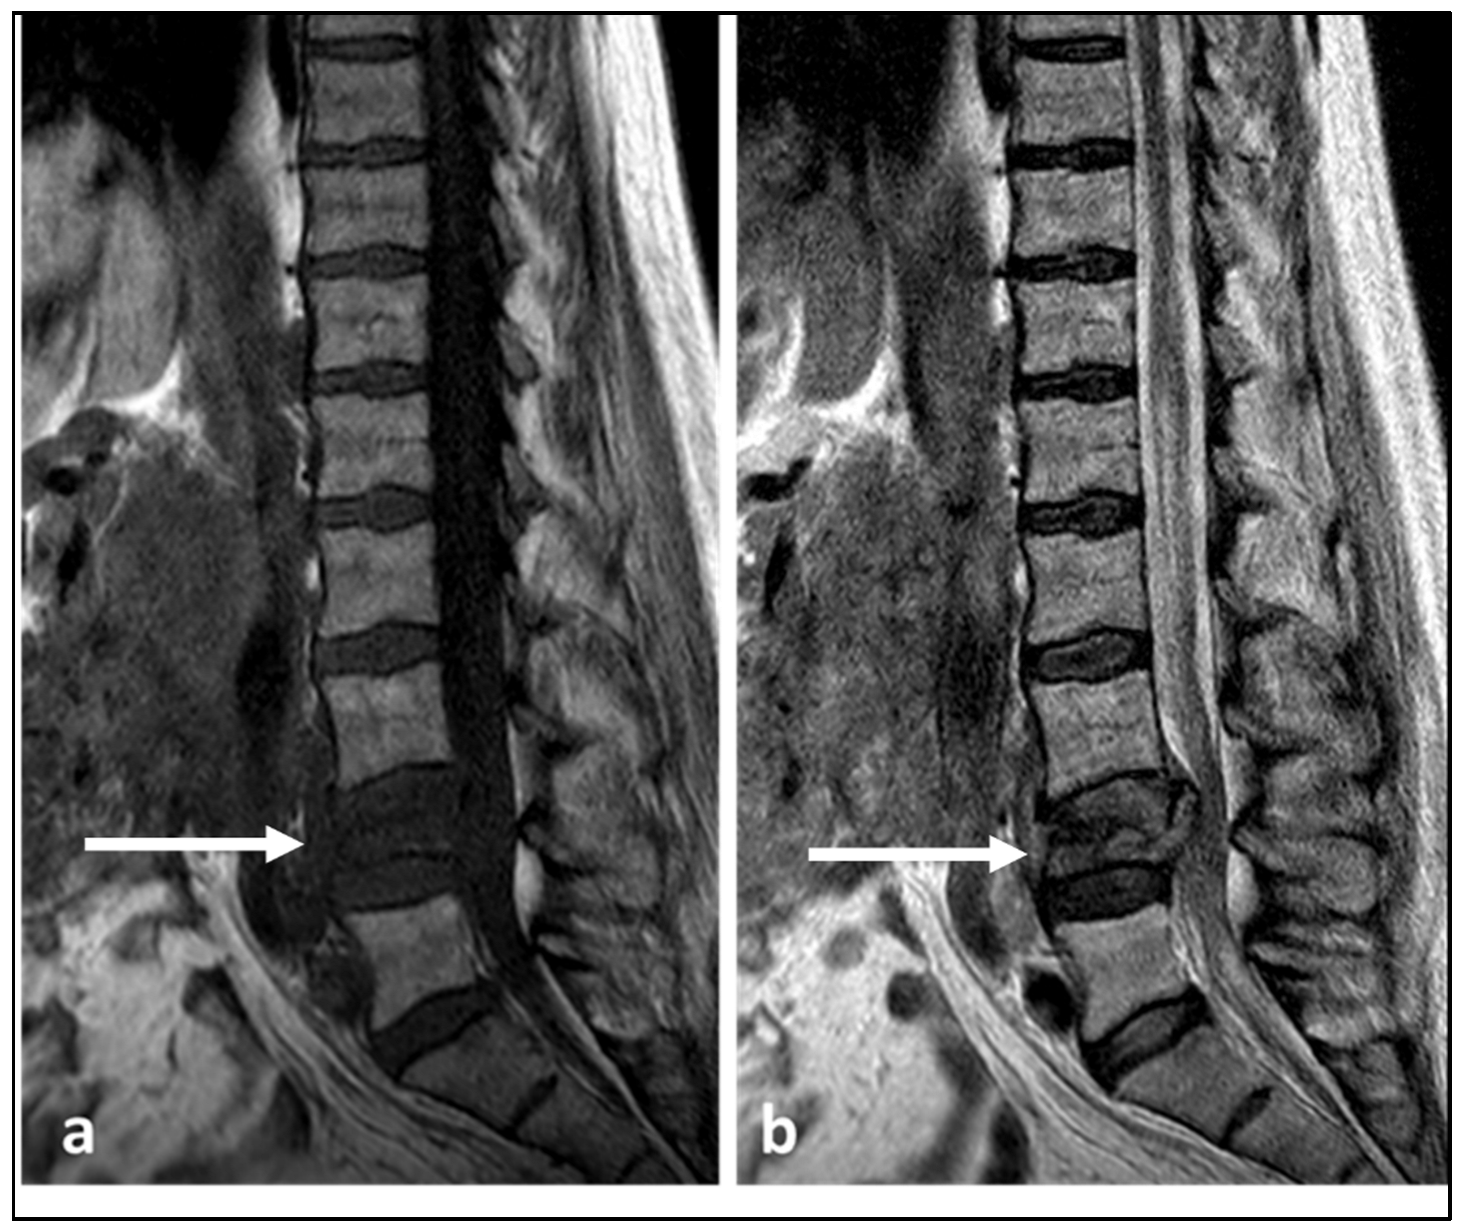

| Lymphoma | Permeative bone loss without overt destruction. | T1 and T2 signal is reduced, but nodular sclerosing lymphoma can be T2 hyperintense. Extra-osseous soft tissue component. |